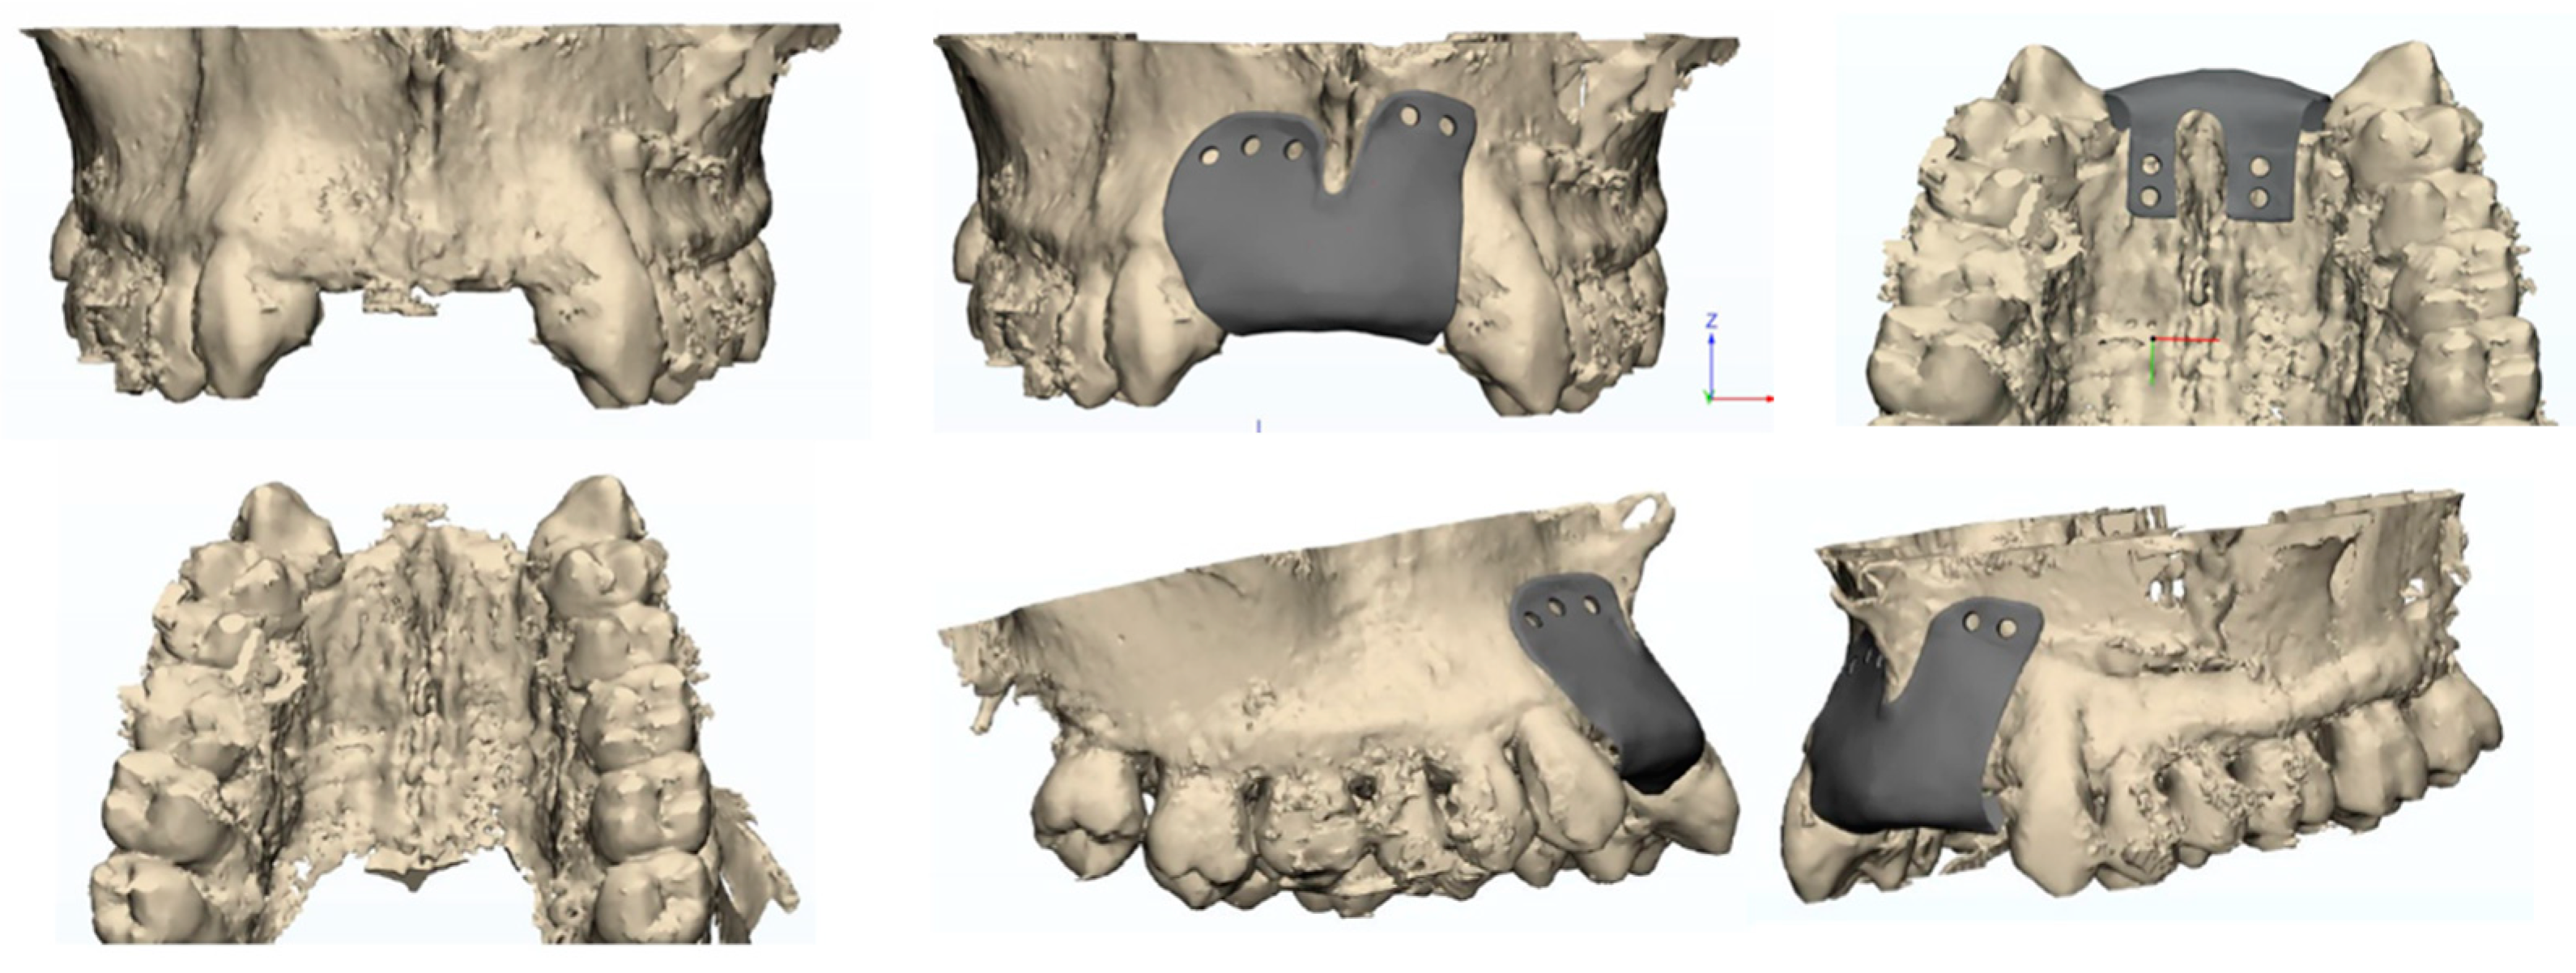

The design and creation of the custom-made membrane (Figure 1) involved a fully digital workflow that began with the previous implant placement planning.

Specifically, the CAD (Computer-Aided Design) 2024 software allows visualization of the 3D virtual model of the patient’s jaws, the digital diagnostic wax-up, and the planned implant position and number. The dental technician team and the dentist could actively collaborate using the software to decide on the most suitable characteristics for the patient. A 3D modeling software 3D CREO Parametric PTC (v.10) has been used.

The prosthetic project played a crucial role in order to choose the correct the height of the mesh. Specifically, the position of the dental elements, pre-visualized through digital wax-up, was used to determine the amount of bone height to be regenerated.

The parameters considered included the following:

1-

The distance between the bone crest and the occlusal plane.

2-

The length of the dental elements in the wax-up.

3-

The implant mucosal tunnel.

This evaluation provided the millimeter value of bone tissue required for regeneration, corresponding to the height of the membrane, and aligned with the previously established prosthetic plan.

Then the CAD modeling software was utilized to design the mesh.

A mesh thickness ranging from 0.2 to 0.7 mm was used for all patients.

A total of 4 occlusive membranes and 6 membranes with a perforated surface were used.

Once the design was approved, the mesh was fabricated from surgical-grade titanium using Selective Laser Melting technology. The membrane was then cleaned, sterilized, and sealed to prevent any contamination before the procedure.

Figure 1. Final design of custom-made mesh.